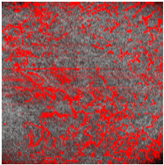

Thus, D-OCT provides images of the superficial vascular plexus. In healthy skin, en-face views show a fine vascular network with decreasing vessel size at each point of arborization (Figure 4a).

Dynamic OCT image visualizing vascular network (all en-face views). (a) Healthy skin with intact vascular plexus, (b) superficial burn with partially disrupted vascular network, (c) deep burn that is totally disrupted, truncated vessels, and (d) deep burn with absent vascular plexus.

Burn injuries may damage the vascular architecture, and the reticular structure may disappear partially (1 point; Figure 4b) or completely (2 points; Figure 4c, d). First, small vessels disappear (Figure 4b), leaving only relatively thick vessels without branches (Figure 4c).

The preservation of the vascular pattern in our patients, as visualized in Figure 4b, was associated with spontaneous wound healing.